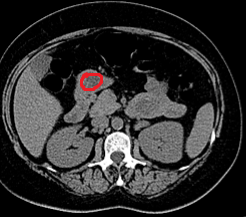

Abdominal CT scan. Red outline – Inflammatory fibroid polyp of the duodenum (Courtesy Dr. V. Penopoulos)